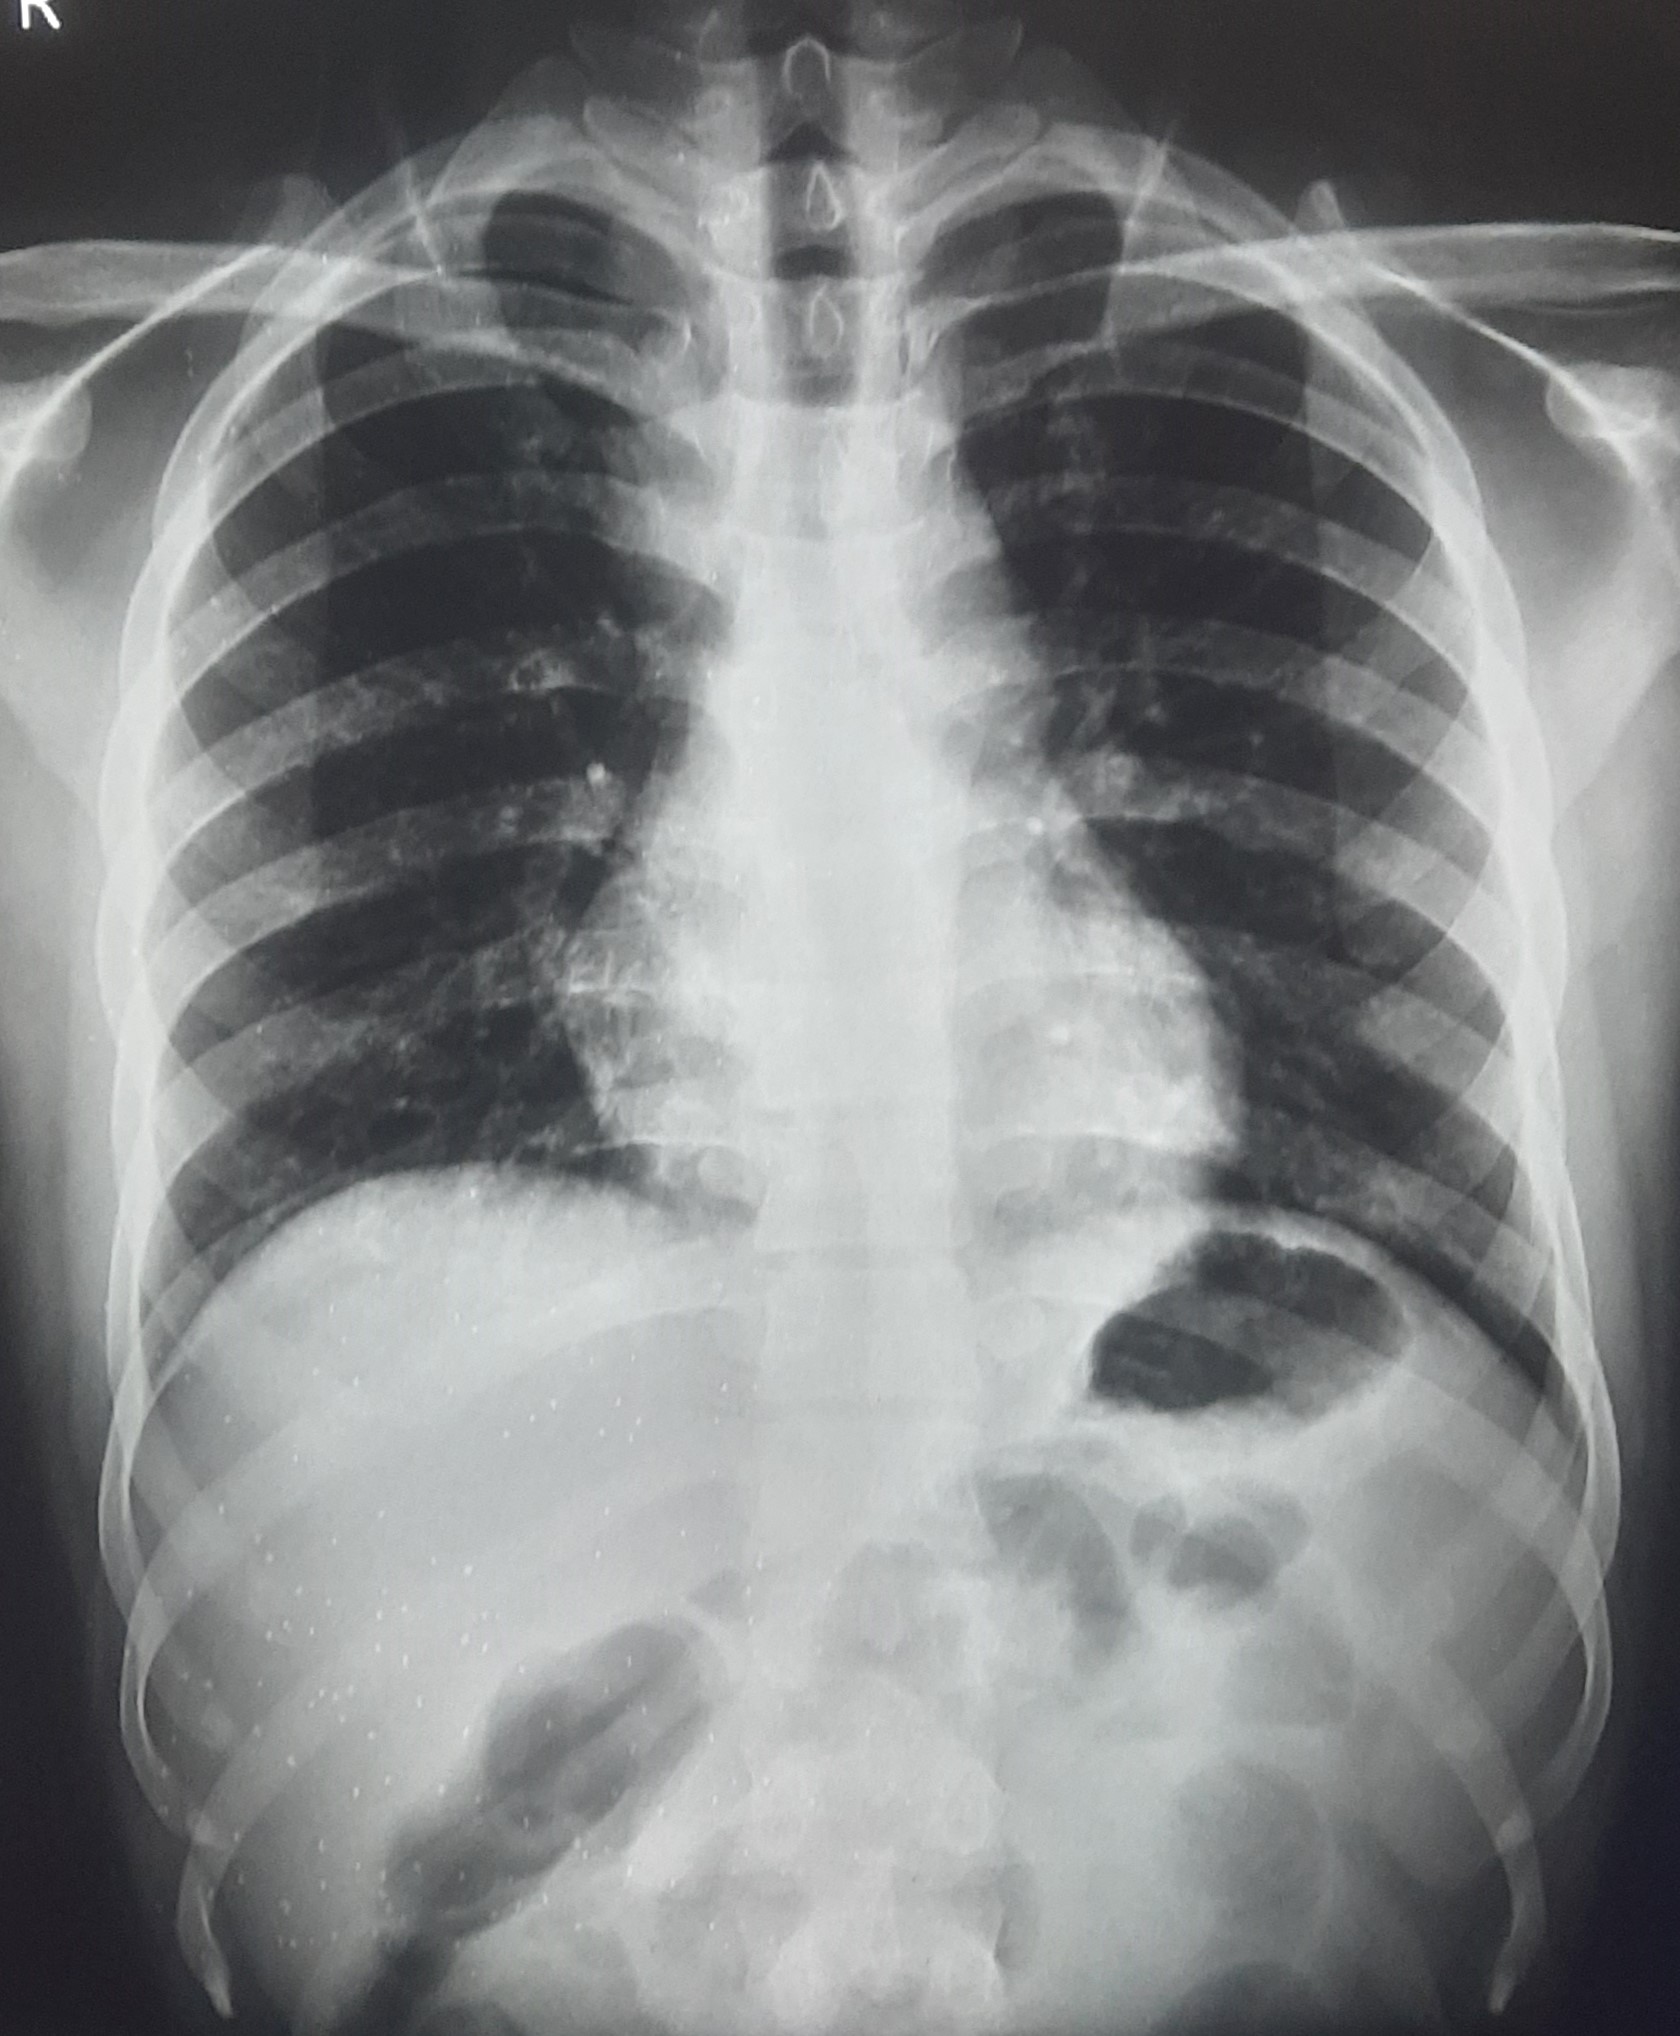

| 262 | IGGMC, Nagpur, Nagpur | P2 | 29-4210 | Mohamad Aslam | Consent taken on Paper | 35 Yrs. |

Provisional Diag : C/O Extra Pulmonary TB

Final Diag : FIBROSIS |

TB Case (Confirmed) | S/O RETICULAR OPACITIES NOTED IN RIGHT UPPER & MIDDLE ZONE/ QUERY FIBROSIS | Abnormality visible on x-ray |